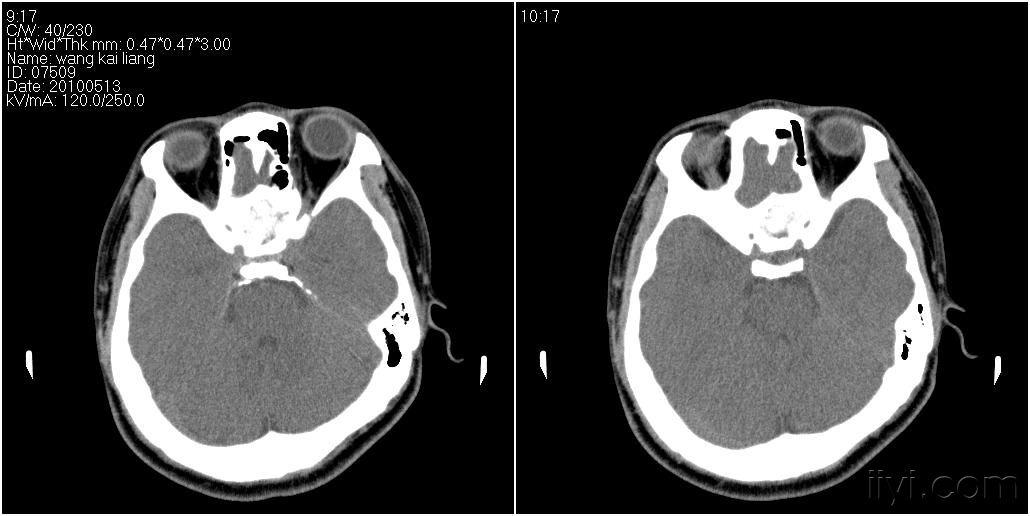

男性27岁患者要求头颅扫描发现蝶窦病变